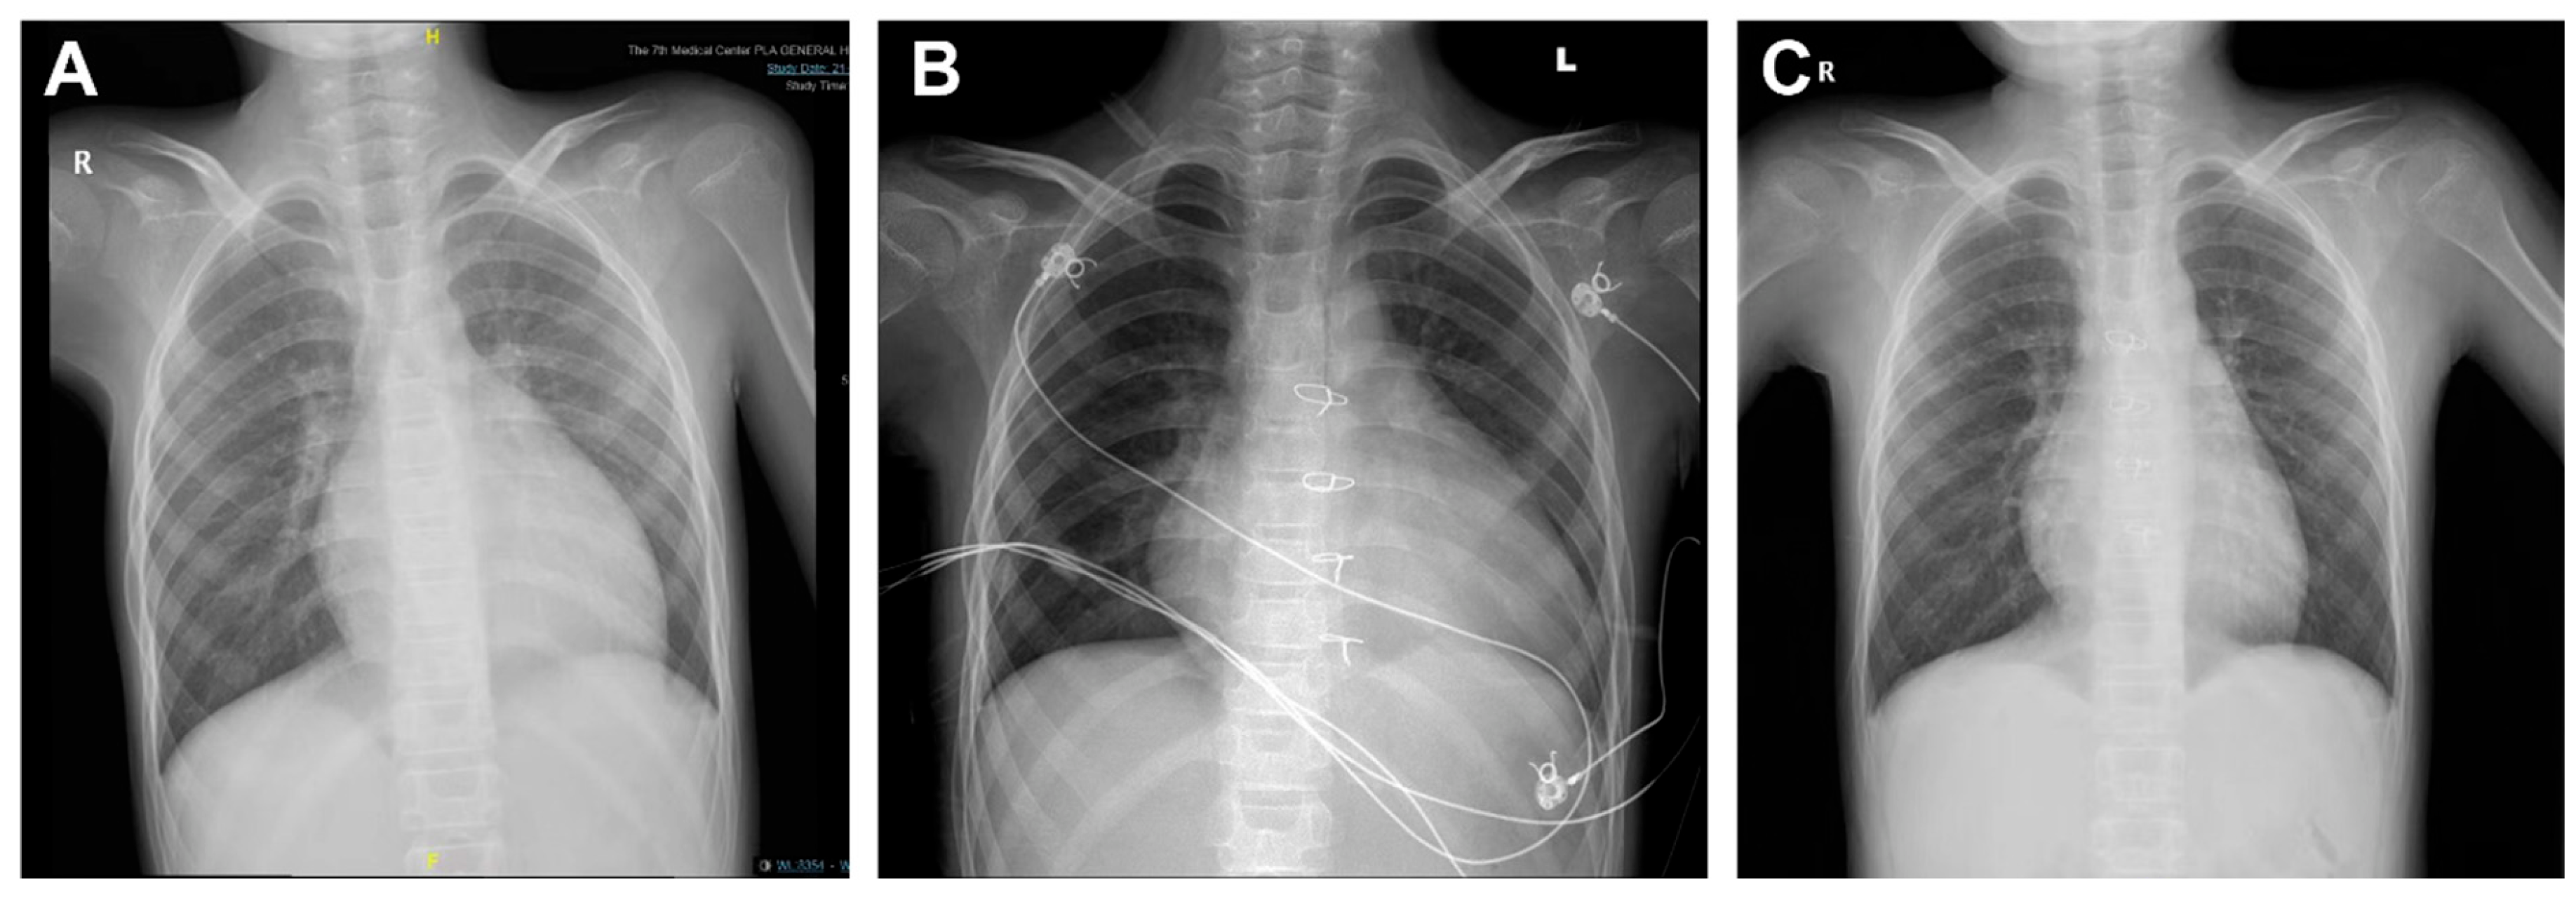

All transplantations were successfully performed. 5 patients underwent ABO-incompatible (ABOi) heart transplants, including one Type B recipient who received a Type O donor heart, 1 Type AB recipient who received a Type A donor heart, and 3 Type A recipients who received Type O donor hearts. Among these, 1 case had the highest DRWR of 3.0. This patient was discharged on postoperative day 28 and returned for a follow-up two months later, with the transplanted heart having resized to fit the recipient’s body (Fig. 1).

Figure 1: Digital radiography (DR) images of patients with maximum donor-recipient weight ratio (DRWR). (A) Pre-transplant DR imaging showing an enlarged heart with an increased cardiothoracic ratio of approximately 0.63. (B) Transplantation of a 19-year-old donor heart (DRWR of 3.0), with a cardiothoracic ratio of 0.75, at 13 days postoperatively. (C) Repeat DR imaging at 2 months post-transplantation, demonstrating the heart restored to the adapted recipient’s size, with a cardiothoracic ratio of approximately 0.57.

Children face unique challenges related to growth and weight changes during development, which often lead to size mismatches between donor and recipient hearts in PHT [23,24]. The DRWR is generally accepted to fall within the range of 0.8 to 1.2. However, the use of larger donor hearts (with DRWR > 1.2) is common in PHT, with studies indicating that more than 50% of pediatric recipients receive hearts from larger donors [25]. Smaller donor hearts, on the other hand, are associated with increased mortality within the first-year post-transplantation. In this study, the average DRWR was 1.38 ± 0.39, with two cases having a DRWR of 0.84. The remaining cases had a DRWR > 1.00, with the highest DRWR reaching 3.0. Notably, the patient with the highest DRWR experienced a successful postoperative recovery and was discharged without complications. Follow-up two months later revealed that the transplanted heart had adapted in size to fit the recipient, demonstrating the heart’s ability to remodel post-transplantation. This finding aligns with other studies, which suggest that donor-recipient size mismatch may not preclude successful outcomes when proper post-transplant management and support are provided [26].